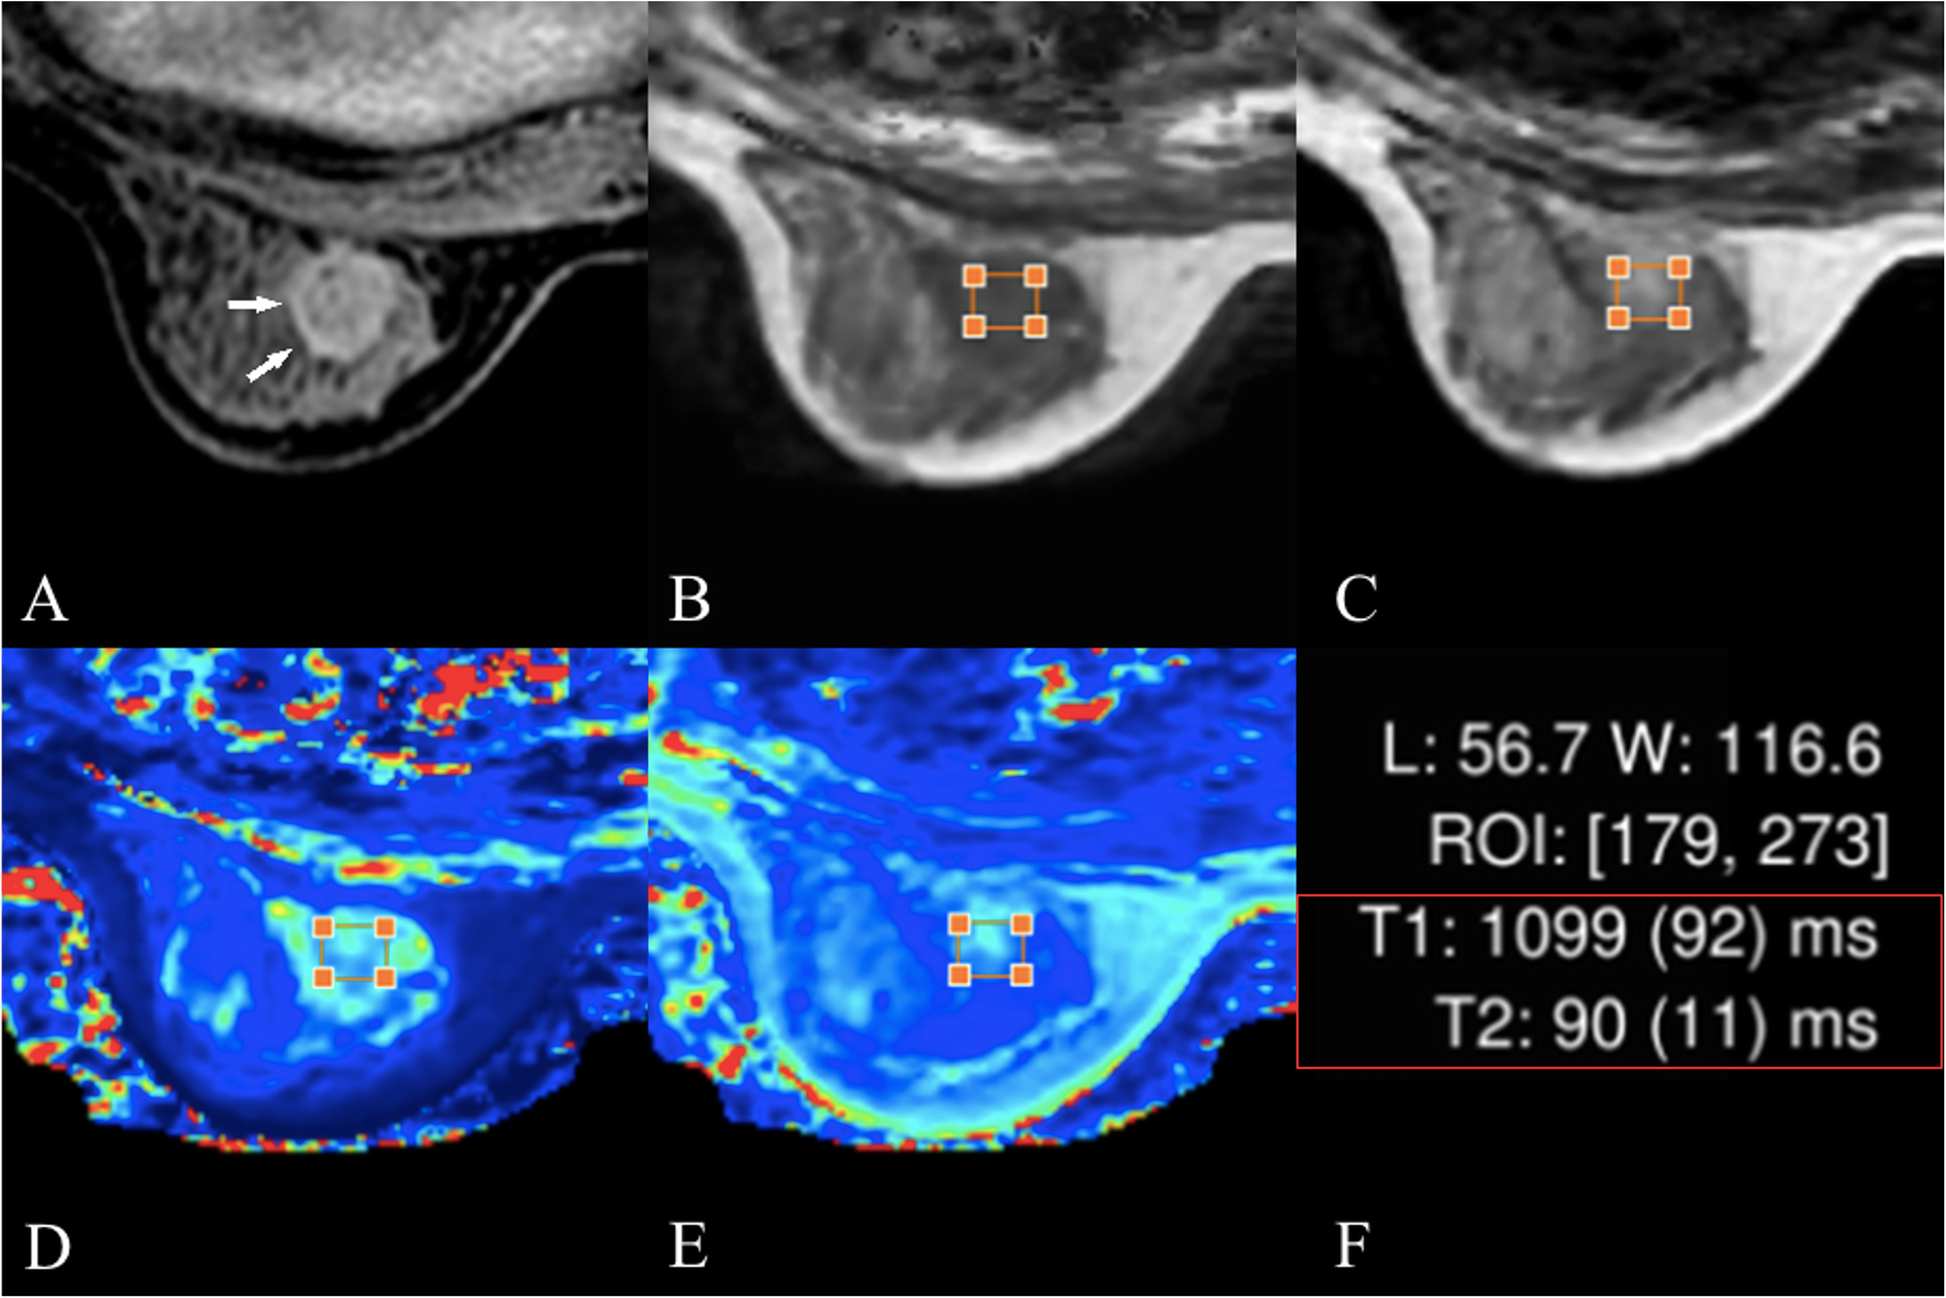

Fig. 2

Female, 50 years old, fibroadenomas. a the lesion is shown using white arrows in the perfusion-enhanced image; b and c, T1-, T2-weighted images obtained from SyMR respectively I; d and e T1 and T2 maps, respectively. The T1 and T2 values are shown in f